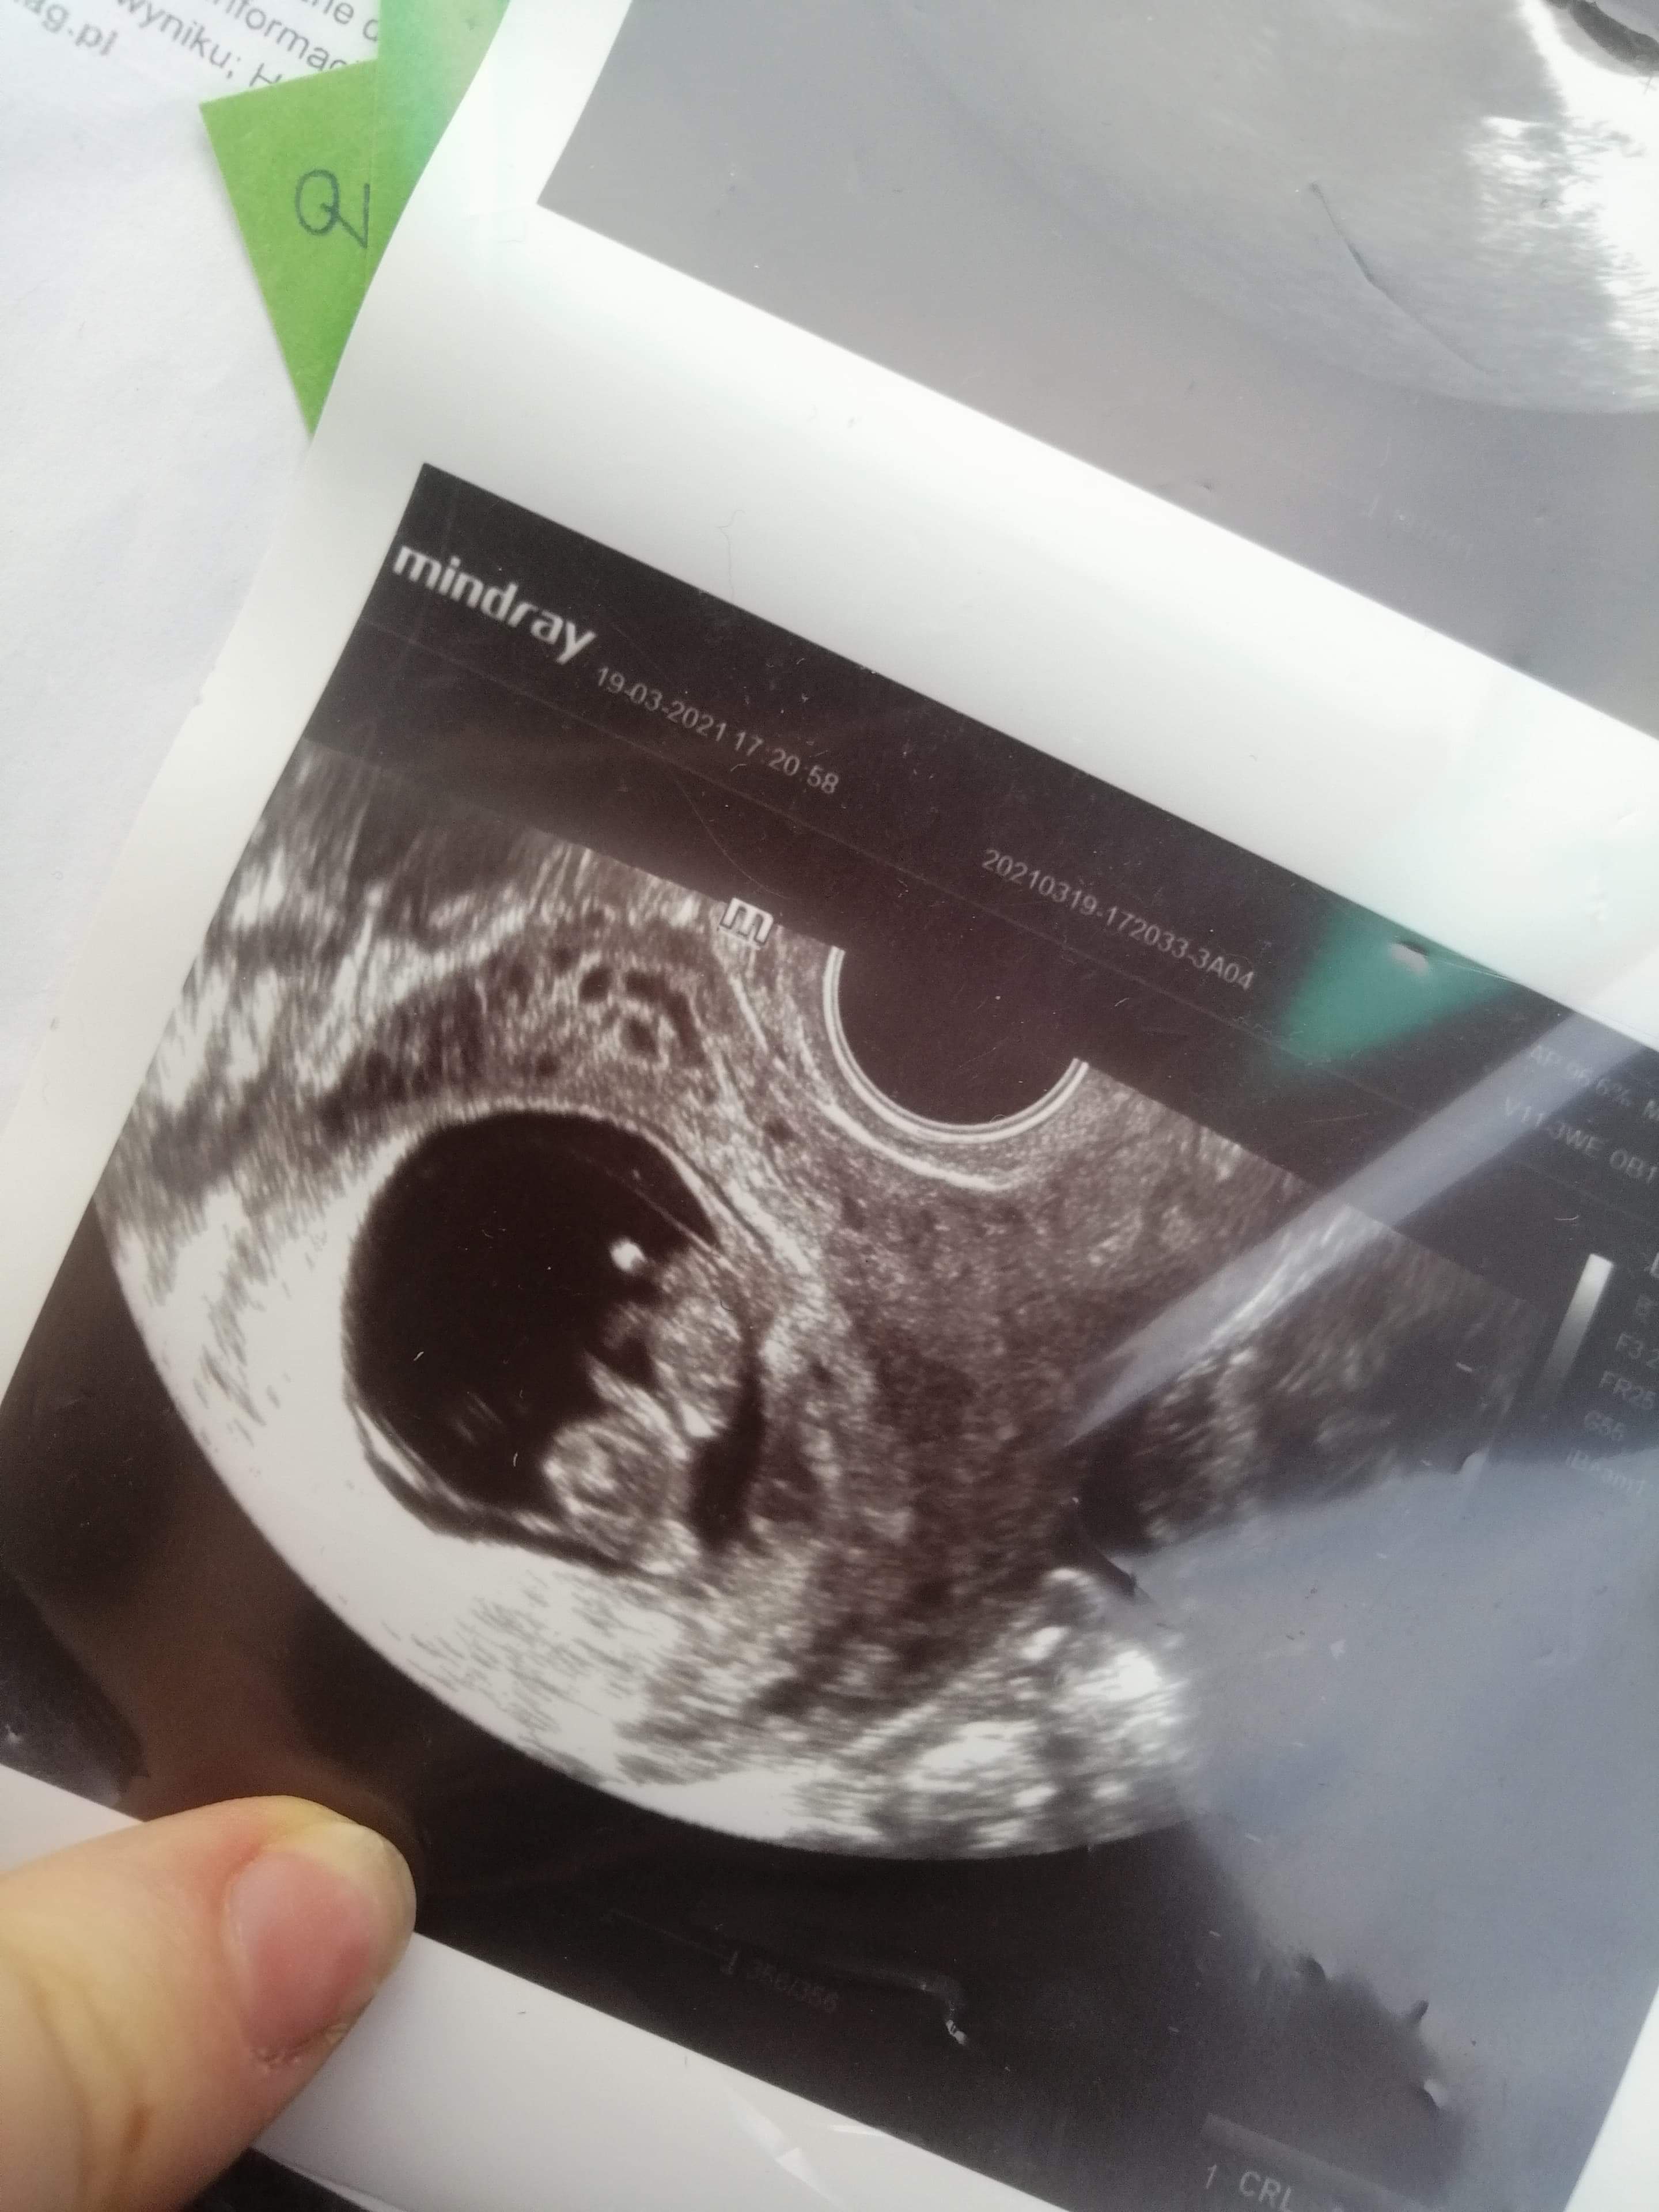

Usg to miałam Xd ale poprzedni lekarz żadnych pappa mi nie kazał robić hyhyJa idę na pappa i usg prenatalne i w sumie tez jestem zielona![]()

Uee Xd czyli tylko stresujące badanieTest PAPP-A to jedno z nieinwazyjnych badańprenatalnych, które służy do określenia ryzyka wystąpienia wad genetycznych u płodu w I trymestrze ciąży. Należą do nich zespoły: Downa, Patau i Edwardsa. Płci nie określa